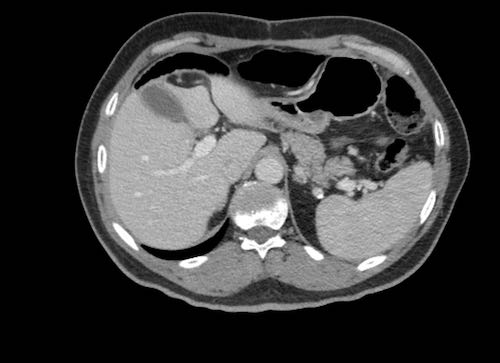

Hình ảnh

Hình ảnh CT của mạc nối bánh nổi trong dịch cổ trướng (mũi tên).

Mạc nối nằm ở bụng trái, trải dài từ bờ ngoài dạ dày xuống phía dưới.

Hình ảnh cho thấy cấu trúc dạng nốt không đồng nhất rõ rệt, điển hình của mạc nối bánh.

Các chấm trắng trong mạc nối có thể là các mạch máu.